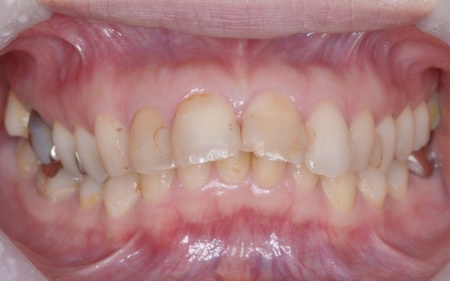

| カウンセリング | 拝見したところ、上前歯が大きく前に出ている上顎前突であり、上下の前歯が噛み合わずに口を閉じても前歯同士が接触しない「開咬(かいこう)」の状態でした。 レントゲン撮影をして詳しく調べた結果、歯の位置だけでなく、骨格的な問題があることが分かりました。 また、前歯で食べ物をうまく噛み切ることができないため、奥歯にも強い負担がかかっているだけでなく、このまま放置すると、奥歯がすり減ったり痛みが生じたりするリスクもあります。 以上のことから、噛み合わせを改善する治療が必要だと診断しました。 |

患者様の場合、骨格的な上顎前突が噛み合わせを乱している主な原因であることから、矯正治療では前歯を後方へ大きく動かすためのスペースを確保する必要があります。 そのため、今回は以下2つの方法を提案しました。 ①抜歯後、アンカースクリューを用いたワイヤー矯正 メリット:骨格的な上顎前突に対応しやすく、前歯を大きく後方へ動かすことができる ②取り外し可能な装置を使用するマウスピース矯正 メリット:装置が透明で目立ちにくく、取り外しができる 以上のメリットとデメリットを丁寧にお伝えしたところ、患者様は①のアンカースクリューを用いたワイヤー矯正を選択されました。 まず、上顎の左右奥歯を抜き、前歯を後方に動かすためのスペースを確保します。 治療の結果、前歯が正しく噛み合うようになり、横顔のバランスも整いました。 矯正治療終了後は、歯が元の場所に戻らないよう上下前歯に保定装置(リテーナー)を装着し、治療を終了しています。 |